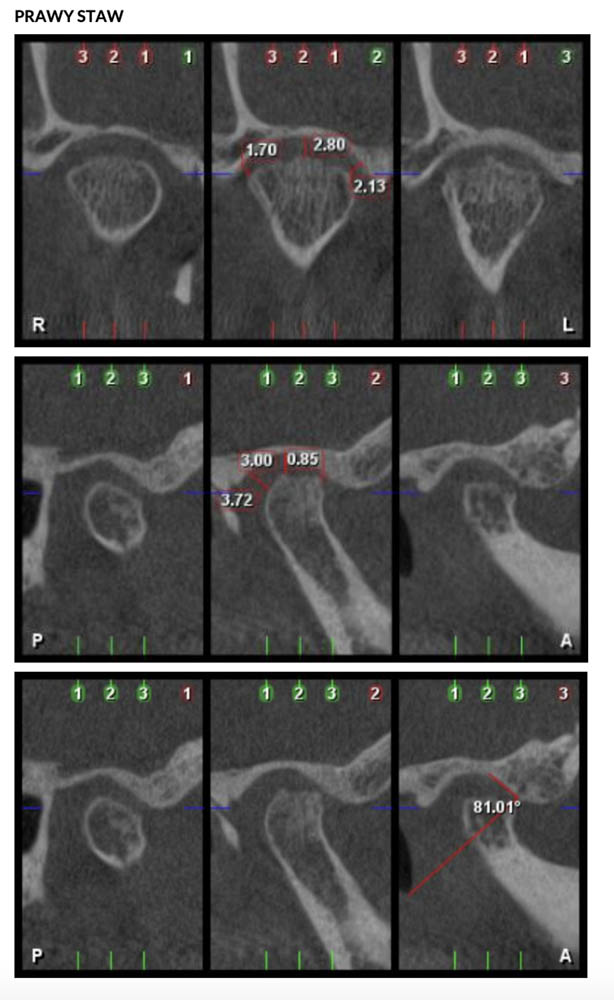

Diagnostyka CBCT i USG